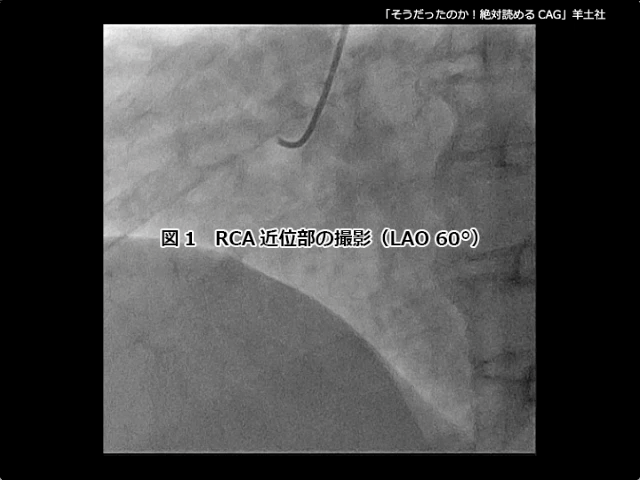

第5章-1 急性冠症候群の造影所見